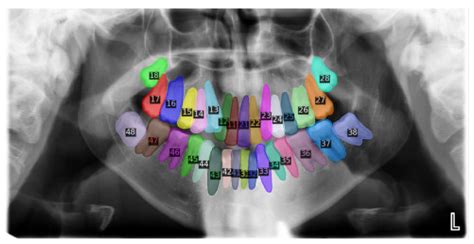

A Panoramic Teeth X Ray, formally known as an orthopantomogram (OPG), is an extraoral radiography technique. The term "extraoral" means the imaging equipment is positioned outside your mouth, unlike traditional dental X-rays where sensors are placed inside the mouth. The machine, known as an orthopantomograph, rotates in a semi-circle around your head, capturing a continuous image of your dental and maxillofacial structures.

This type of imaging is incredibly versatile because it provides a broad overview of the facial anatomy. It is an essential diagnostic tool for identifying issues that are not immediately visible during a standard clinical check-up. By capturing everything from sinus cavities to the roots of the wisdom teeth, it gives the dentist a holistic view of your oral environment.

Once the images are generated, your dentist will examine them for any abnormalities. Because the image is an orthopantomogram, it flattens the curved jaw into a two-dimensional plane. This allows the dentist to compare the symmetry of the left and right sides of your mouth. They will look for: